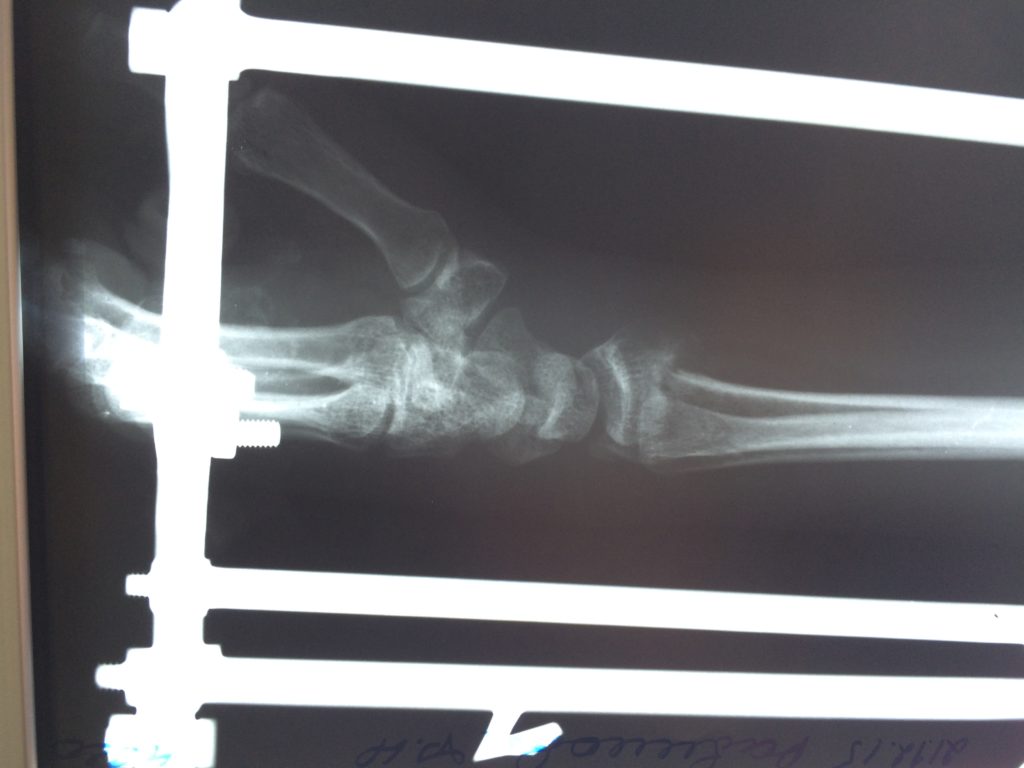

Операция - открытая репозиция, остеосинтез лучевой кости пластиной с костной ксенопластикой материалом "Остеоматрикс". На контрольных снимках в три месяца имеется консолидация перелома, миграции фиксатора нет, имеется остеоинтеграция ксенопластического материала.

Отдаленные результаты через 3 (три) месяца: